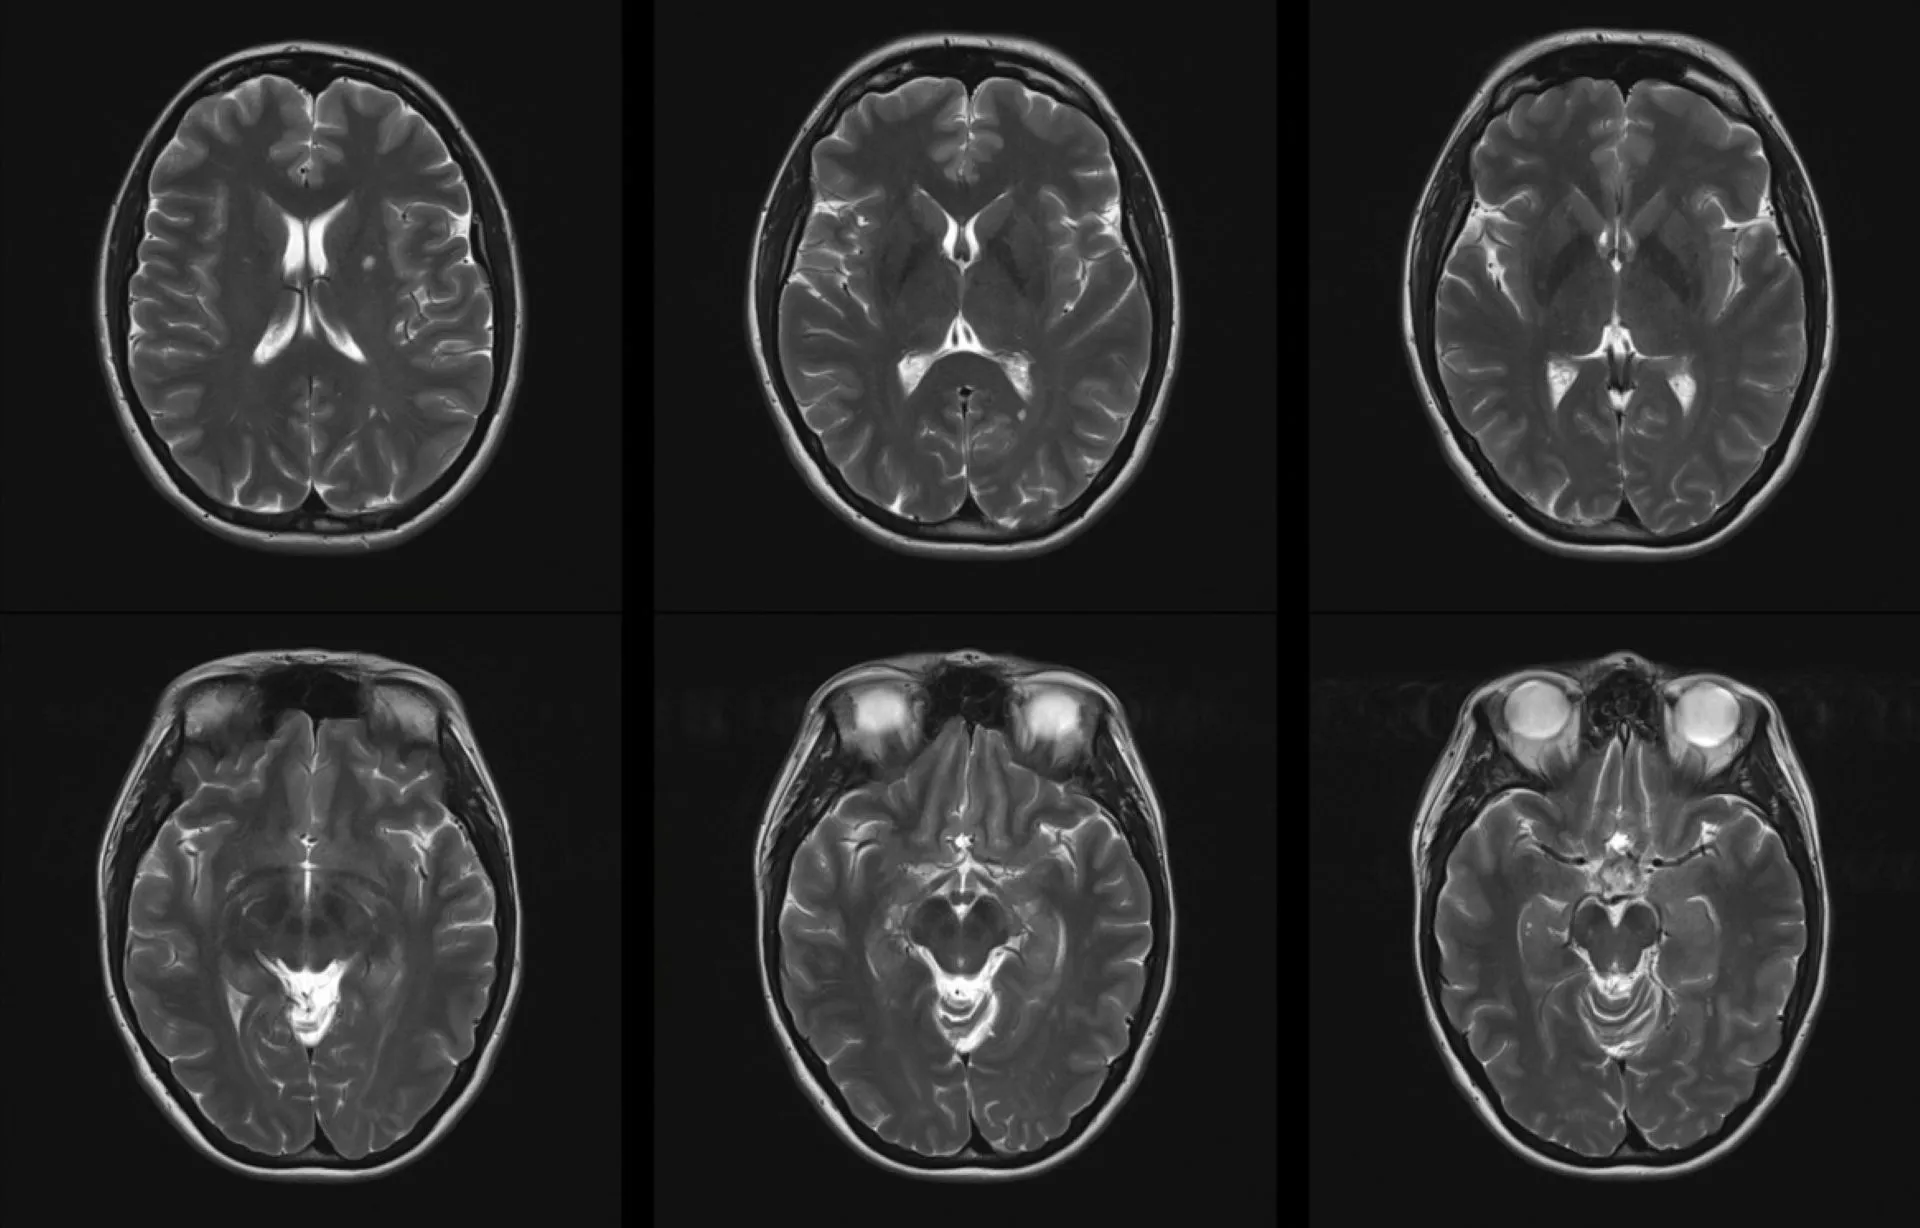

La pollution de l’air est souvent désignée comme un « tueur invisible », et les dernières recherches renforcent cette image. Une étude récente a mis en évidence un lien préoccupant entre l’exposition à l’air pollué et le risque de développer la sclérose en plaques (SEP). Elle souligne également que la pollution peut aggravé la condition chez les personnes déjà atteintes.

Les résultats révèlent qu’une exposition prolongée aux particules fines (PM2.5) augmente le risque de SEP de 21 %. Pour des particules légèrement plus grosses, d’un diamètre inférieur à 10 micromètres, ce risque grimpe à 20 %. Cependant, pour d’autres polluants tels que le monoxyde de carbone ou le dioxyde de soufre, aucune association significative n’a été trouvée pour le développement de la maladie. En revanche, les personnes déjà atteintes de SEP voient leur santé se détériorer lorsqu’elles sont exposées à ces polluants de manière temporaire, ce qui peut entraîner des lésions et une augmentation des risques de rechute.

Le message des experts en santé publique est clair : un air plus pur est crucial. Cette étude offre des preuves solides soutenant l’idée que la pollution de l’air peut non seulement déclencher la sclérose en plaques, mais également augmenter son intensité et sa sévérité, notamment par le biais des rechutes et de la progression des incapacités.